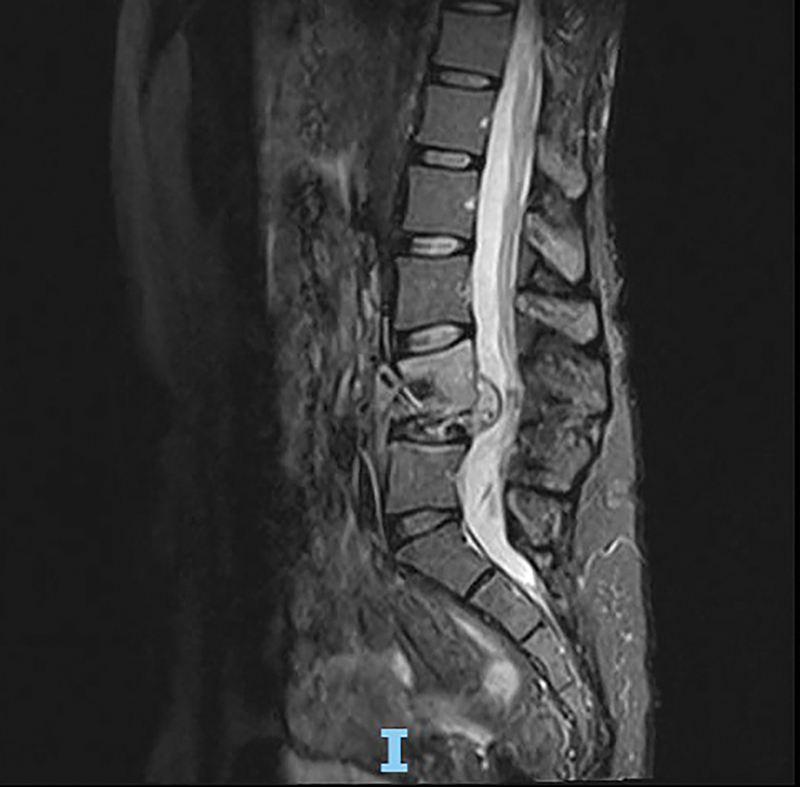

结核病(TB)是一种由结核分枝杆菌复合体引起的慢性感染,在影响免疫系统的情况下,如多发性硬化症,以及用疾病缓解药物(dmd)治疗结核病,结核病再激活的风险增加。本研究是一项回顾性研究,对1994年2月至2023年9月期间在圣保罗联邦大学圣保罗医学院神经内科和神经外科诊断为多发性硬化症的2036例患者进行了随访。其中6例纳入本病例系列,服用不同的dmd: fingolimod (n = 2)、干扰素β 1a (n = 2)、醋酸格拉替默(n = 1)和环磷酰胺(n = 1)。在我们的研究中,两名患者在结核病治疗过程中残疾加重,另外三名患者在完成治疗后残疾加重。我们强调筛查所有符合DMD治疗条件的患者的重要性,特别是高效的现代治疗,以及制定基于研究的MS患者传染病筛查指南的重要性。

Tuberculosis (TB), a chronic infection caused by the Mycobacterium tuberculosis complex, has an increased risk of reactivation in conditions that affect the immune system, such as MS, and its treatment with disease-modifying drugs (DMDs). The present is a retrospective study of 2,036 patients diagnosed with MS followed at the Department of Neurology and Neurosurgery of Escola Paulista de Medicina, Universidade Federal de São Paulo, from February 1994 to September 2023. Of that total, 6 were included in this case series, taking different DMDs: fingolimod (n = 2), interferon beta 1a (n = 2), glatiramer acetate (n = 1) and cyclophosphamide (n = 1). In our study, two patients experienced worsening disability during tuberculosis treatment, while three others had increased disability after completing treatment. We reinforce the importance of screening all patients eligible for DMD treatment, especially the highly effective modern ones, and the importance of developing research-based guidelines for screening infectious diseases among patients with MS.